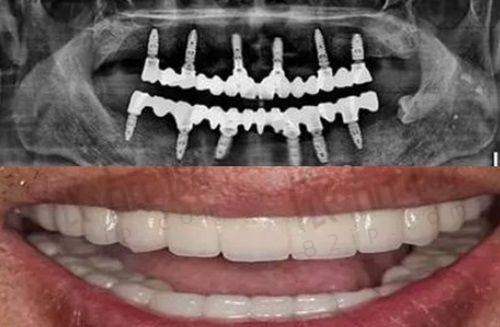

牙齿冷光美白是一种常见的牙齿美白方法。它的原理是通过冷光将药物渗透到牙齿组织中去,从而达到美白牙齿的成效。这种方法与传统的牙齿美白方法相比,具有特别多优势。

首先,冷光美白的过程相对安心。在整个美白过程中,采用的是低温冷光,不会对牙齿和牙龈造成损伤。而且,使用的美白药物也是经过严格检测和筛选的,对人体的刺激性较小。

其次,冷光美白的成效显著。一般来说,经过一次冷光美白治疗,牙齿能够提高几个色阶,让牙齿变得更加洁白亮丽。而且,这种美白成效能够持续较长的时间,只要患者在术后注意口腔护理,就能够保持牙齿的美白成效。

强调美白成效与长期维护:芜湖芜优口腔在进行牙齿冷光美白时,不仅仅是追求短期的美白成效,更注重牙齿的长期维护。医生会根据患者的牙齿情况和个人需求,制定个性化的美白方案。在美白过程中,会严格控制药物的使用剂量和冷光的照射时间,确保美白成效的同时,减少对牙齿的损伤。而且,在美白治疗后,医生会为患者提供详细的口腔护理建议,包括正确的刷牙方法、使用牙线、定期洗牙等,帮助患者保持牙齿的美白成效,延长美白的持续时间。